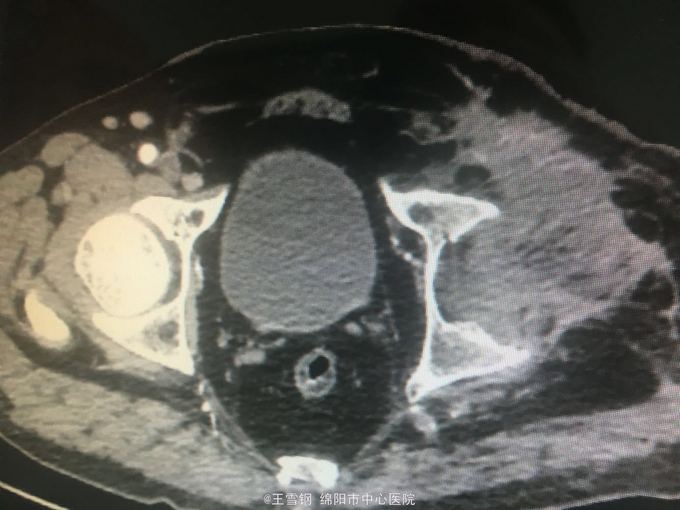

男,66岁,左下肢高位截肢术后2年,人工血管感染1年 患者2年前因外伤行左下肢高位截肢,同时伴有血管损伤,行人工血管转流,1年前腹部伤口反复出现感染,间断有脓性分泌物及血性液体流出,无明显寒战高热

下腹部可见人工血管突出体表约3cm,伴有血性液体及脓性分泌物流出 完成CT检查

左下肢截肢术后;人工血管感染; 全麻下行人工血管取出、局部清创术